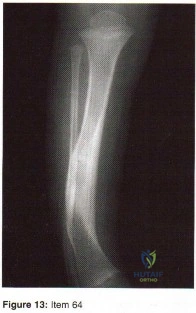

- Ewings tumor

- Parosteal osteosarcoma

- Dedifferentiated chondrosarcoma

- Low grade intramedullary chondrosarcoma

- High grade intramedullary osteosarcoma